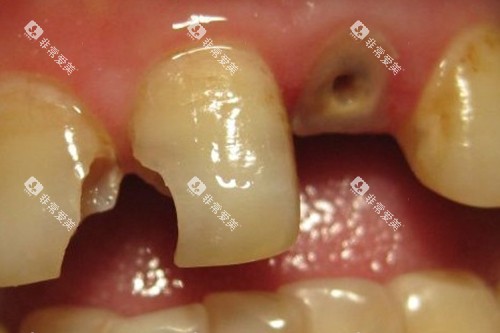

无论是常见的牙齿矫正、补牙、拔牙,还是较为复杂的种植牙手术,医生们都能熟练操作。

在治疗方面,医院拥有多种治疗项目,如牙齿美白、牙周治疗等。